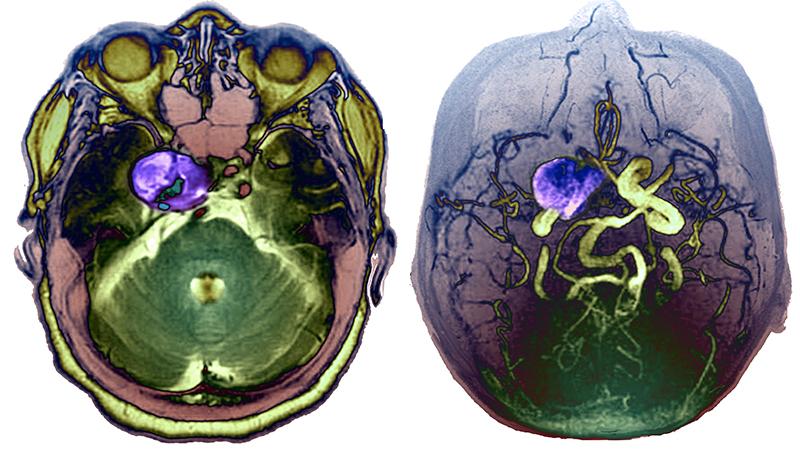

Brain regions showing metabolic adaptation during the transition to menopause

Weill Cornell Medicine neurology faculty reveal menopause is a dynamic neurological transition that significantly impacts brain structure, connectivity, and the metabolic profile during midlife endocrine aging of the female brain. The researchers used multimodality imaging to better understand the transition from pre- to post-menopause, with its steep decline in estrogen production. The study involved brain scans of women pre-, peri-, and post-menopausal. The results suggest that changes occur in many brain areas throughout the menopause transition. These include lower gray matter volume on average from the pre-menopausal to the post-menopausal group in the inferior temporal gyrus. A decline in glucose use was also noted from pre- to post-menopause over large portions of the temporal lobes as well as a decline in white matter volume in multiple regions throughout the brain. This study shows how menopause reshapes the landscape of the female brain and hints, at least, that this reshaping includes compensatory adaptations that maintain brain function despite the menopause-related drop in estrogen levels.

Brain regions showing metabolic adaptation during the transition to menopause (Courtesy of Dr. Lisa Mosconi)